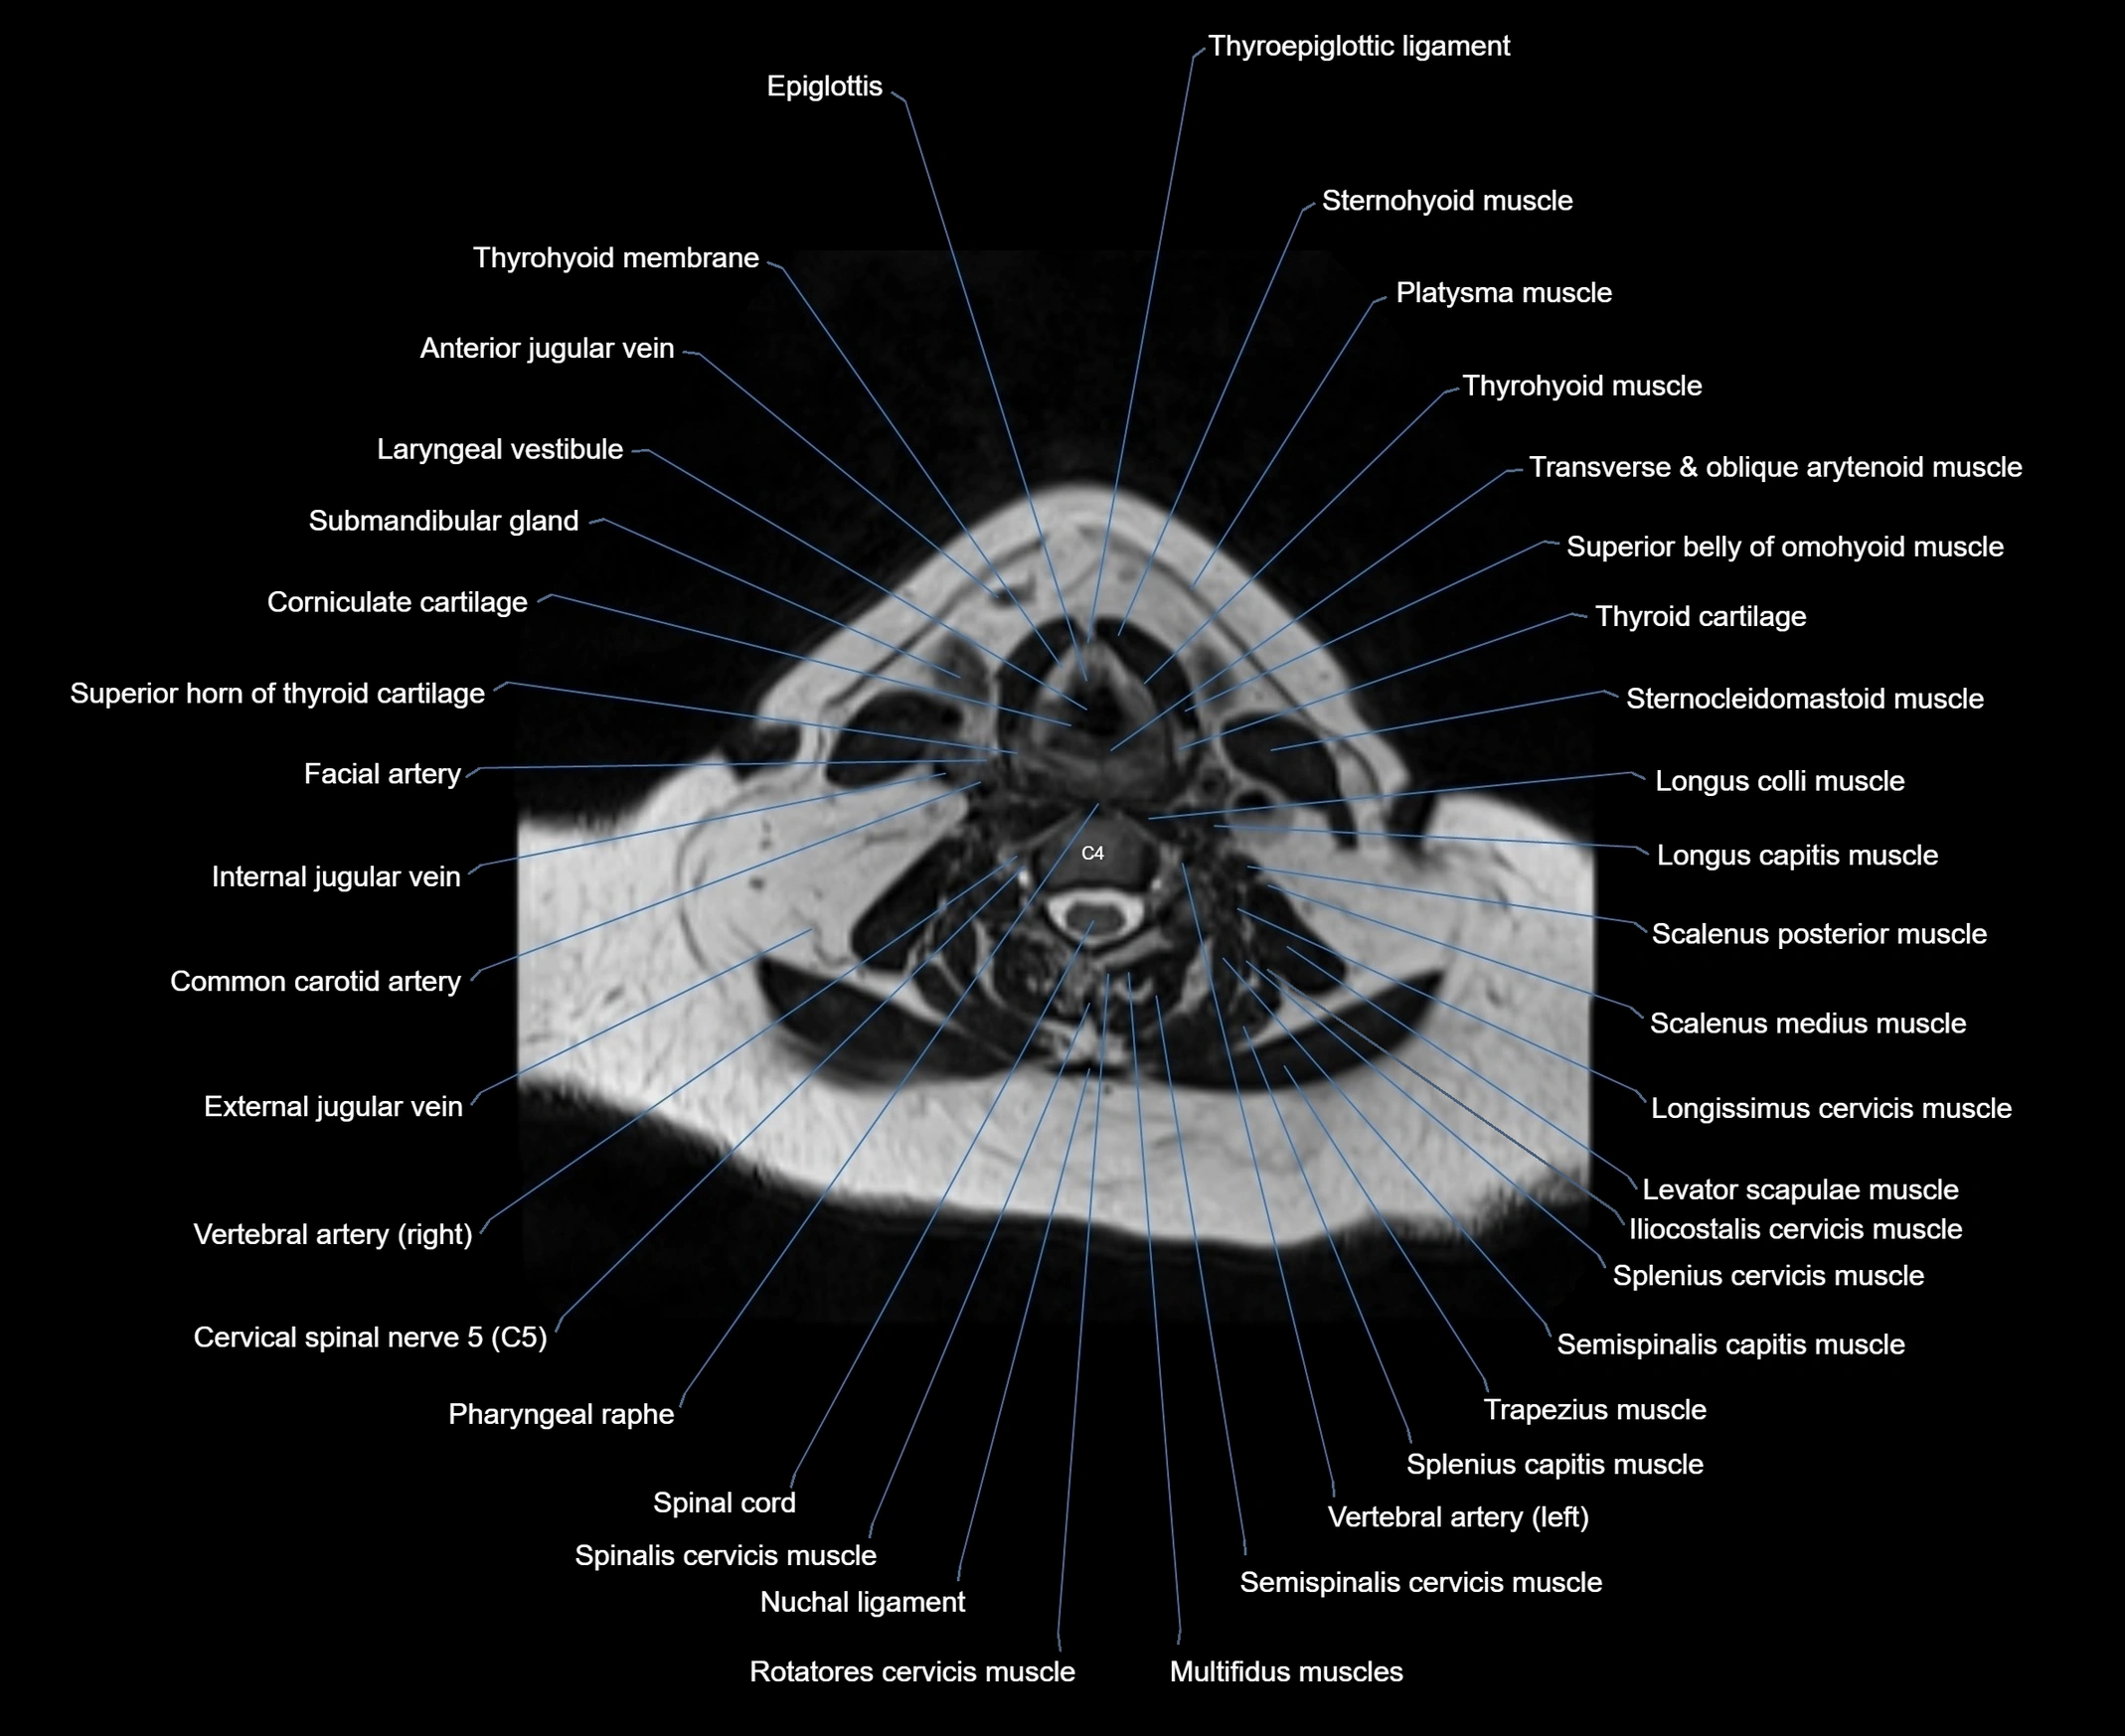

- Cervical spinal nerve 4 (C4)

- Cervical spinal nerve 5 (C5)

- Common carotid artery

- Epiglottis

- External jugular vein

- Inferior belly of omohyoid muscle

- Inferior constrictor muscle of pharynx

- Laryngeal vestibule

- Longus capitis muscle

- Longus colli muscle

- Multifidus muscles

- Oblique and transverse arytenoid muscles

- Pharyngeal raphe

- Rotatores cervicis muscle

- Scalenus medius muscle (middle scalene muscle)

- Scalenus posterior muscle (Posterior scalene muscle)

- Semispinalis capitis muscle

- Semispinalis cervicis muscle

- Spinal cord

- Spinalis cervicis muscle

- Splenius cervicis muscle

- Sternocleidomastoid muscle

- Superior belly of omohyoid muscle

- Thyroepiglottic ligament

- Thyrohyoid membrane

- Thyrohyoid muscle

- Thyroid cartilage

- Trapezius muscle